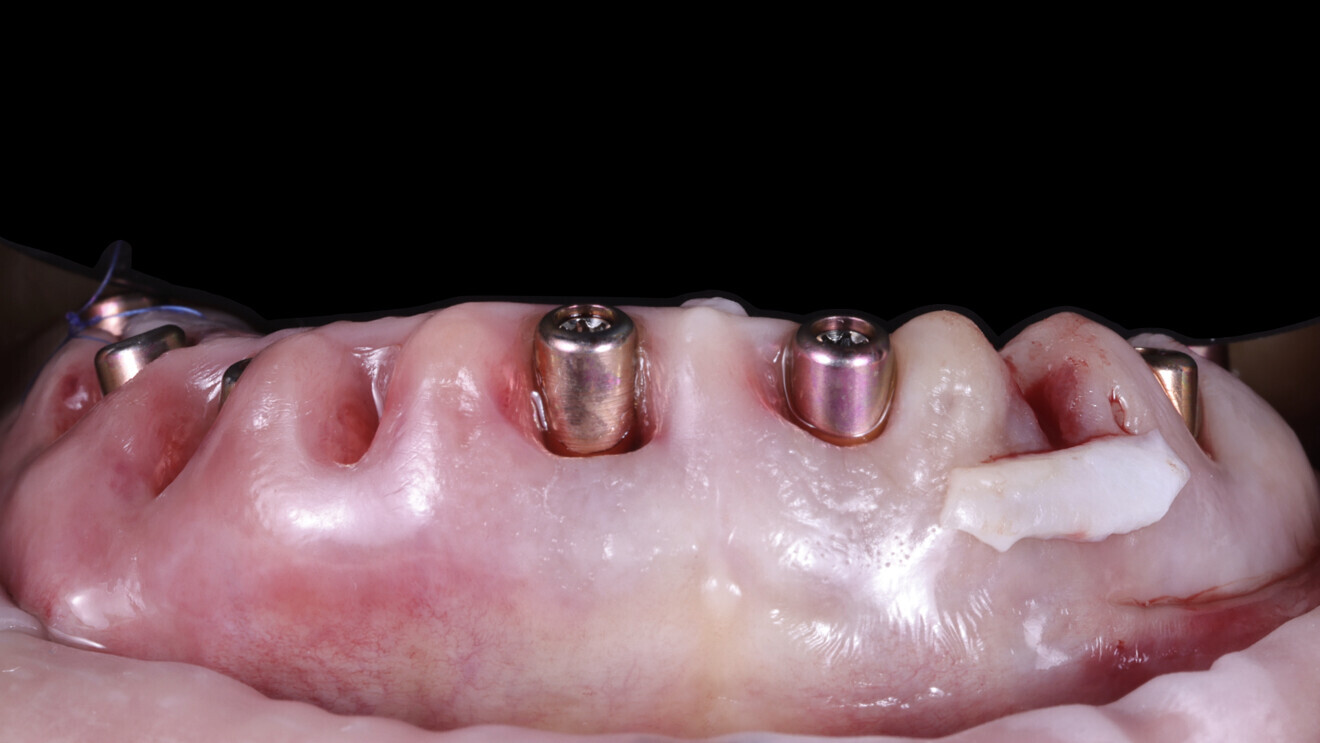

4. Guided implant placement: Eight implants were placed using a guided approach, achieving optimal progressive torque of 35 N cm and excellent bone–implant contact (Fig. 17).

5. Multi-unit abutment seating: The multi-unit abutments were torqued to 25 N cm.

6. Placement of SmartFlag scan bodies: The scan bodies were attached. The remaining teeth served as reference points for the dental technician to align the digital impression with the preplanned design and fabricate the temporary restoration.

7. Final tooth extractions: The remaining teeth were extracted to ensure a clean surgical site, and healing abutments were placed on the implants (Fig. 18).